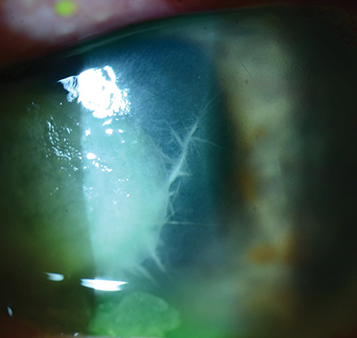

Crystals are seen in subepithelial and/or stromal regions of the cornea. May or may not have an overlying epithelial defect. In the presence of a corneal transplant, the crystalline opacities frequently are localized emanating from an existing suture track (see Figure 4.15.1).

Infectious crystalline keratopathy: Seen in corneal grafts and chronically inflamed corneas. Streptococcus viridans is the most common organism; other organisms include Staphylococcus epidermidis, Corynebacterium species, Pseudomonas aeruginosa, and fungi. Atypical mycobacteria and Alternaria have been reported after LASIK.